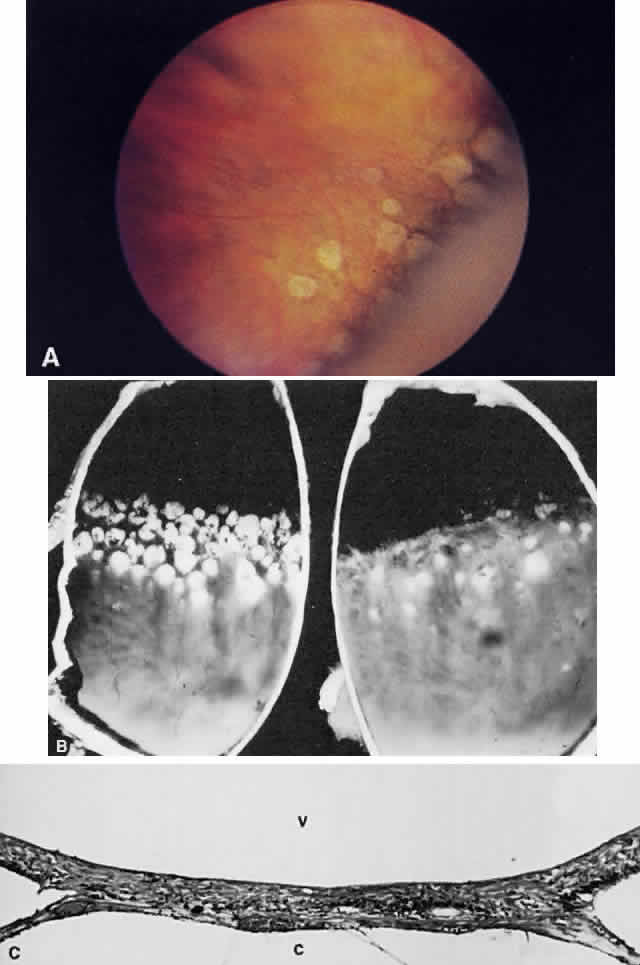

Three distinctive retinal degenerations occur frequently in the periphery: peripheral cystoid degeneration, lattice degeneration, and paving stone degeneration.

Typical cystoid degeneration involves the formation of cyst-like spaces at the level of the outer plexiform layer (Blessig-Iwanoff cysts) (Fig. 59). These are common lesions, present in most persons from the first decade of life. These “cysts” appear to become more numerous with age. Coalescence of these cysts may result in “senile” retinoschisis.23 Reticular cystoid degeneration involves a disruption at the level of the nerve fiber layer. It is located frequently just posterior to the area of typical cystoid degeneration. A network of fine, branching blood vessels is seen commonly over the surface of reticular cystoid degeneration.

Fig. 59. A. Typical cystoid degeneration of the peripheral retina with cyst-like spaces in the outer plexiform layer (Blessig-Iwanoff cysts). These cysts sometimes coalesce, and the inner layer breaks down to form a hole. B. Peripheral cystoid degeneration with atrophic holes. (A, courtesy of Ralph C. Eagle Jr, MD, Philadelphia, PA. B, courtesy of William Tasman, MD, Philadelphia, PA).

Degenerative or senile retinoschisis involves a splitting of the retina at the level of the outer plexiform layer for a distance of at least one disc diameter. As seen ophthalmoscopically, degenerative retinoschisis frequently has a “beaten metal” appearance, and fine, white dots may be seen within the cavity. These dots are thought to represent columns of Müller cells that have been stretched to the point of rupture: the clinically observed dots are Müller cell remnants that remain adherent to the internal limiting membrane. These Müller columns are believed to be responsible for the unevenness of the outer schisis surface; the inner surface is typically smooth. Large holes in the outer wall of the schisis cavity (by convention, “outer” refers to the scleral side of a retinal lesion whereas “inner” refers to the vitreous side of the retina) are frequently observed (Fig. 60), although smaller inner layer holes are less common. The presence of holes in both the inner and outer walls of a schisis cavity creates a pathway from the vitreous to the subretinal space, and a rhegmatogenous retinal detachment may develop.

Fig. 60. A. Photomicrograph of a retinoschisis cavity with a hole in the outer layer (OL). The inner layer (IL) is intact. Typical peripheral cystoid degeneration is present (arrow). B. Outer wall holes in a patient with senile retinoschisis. Notice the pocked marked appearance of the outer wall layer peripheral to the holes. (B, courtesy of William Benson, Philadelphia, PA, Wills Eye Atlas of Ophthalmology. Lippincott-Raven Fig 4-58, 1996)